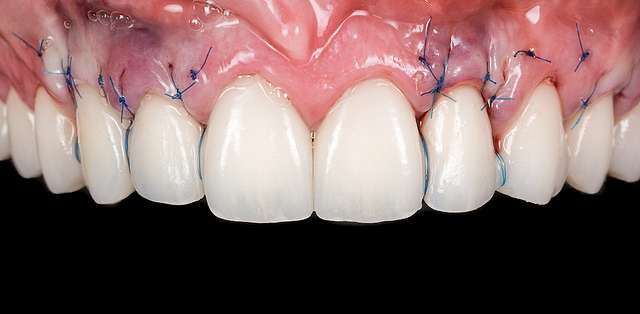

A gingival graft is a micro-surgery that will transplant a bulk of soft tissue - free gingiva or connective tissue ( the internal layer of gingiva ) to cover a soft tissue defect. Usually this type of procedures is required to augment implants, or to cover defects caused by periodontal disease or trauma. The grafts are harvested from the third molar region or the palate, and are transported where they are needed.

This type of procedure is a very delicate one, using the same type of blades like the ones used in ophthalmology and the sutures are also very thin. The sutures will be removed after 7-14 days, depending on the case, when primary healing is achieved. The maturation of the graft will take roughly 90 days, this is the reason why, when placing implants we prefer to also do the graft, so we can sync the healing time for both procedures.

Using tissue grafts to correct tissue defects

Using tissue grafts to correct gingival levels or cover recessions